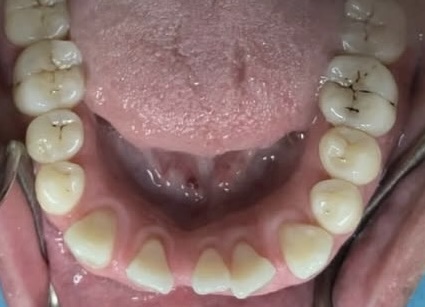

Crowding and constricted arch. Comprehensive orthodontic treatment was performed, and teeth alignment was restored.